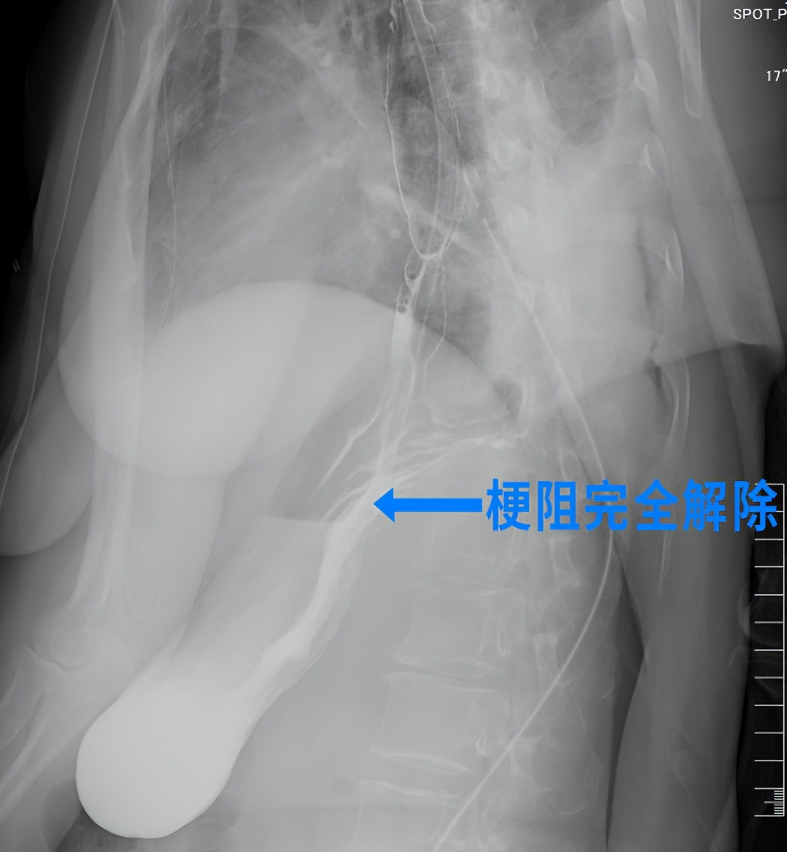

术后,护理团队遵循加速康复外科路径,为王阿姨启动个性化康复计划,从疼痛管理、营养支持到呼吸功能训练进行全流程精细化管理。术后造影结果显示,王阿姨的贲门梗阻已完全解除,术后48小时便能正常进食,困扰她一年多的进食难题终于得到根治。